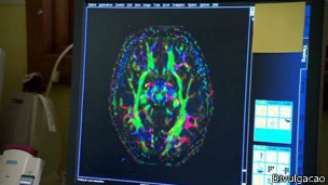

Os especialistas vão utilizar ressonância magnética para estudar o cérebro dos jovens

"Exames de ressonância magnética nos permitirão obter boas imagens de como a anatomia do cérebro muda ao longo do desenvolvimento do indivíduo", disse Bullmore à BBC. "Estamos particularmente interessados em entender quais são as alterações no tecido da parte central do cérebro, conhecido como massa branca."